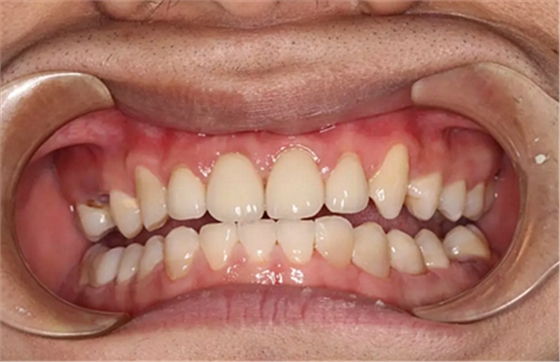

現(xiàn)在剩下的任務(wù)就是為我其他的兄弟姐妹們治療了。需要做根管的做根管,需要做冠的做冠,需要樹脂充填的做樹脂充填。前前后后主人帶我們進(jìn)行了12次的復(fù)診,歷時(shí)6個(gè)月,現(xiàn)在的我們是這樣的

再來看看曾經(jīng)的我們